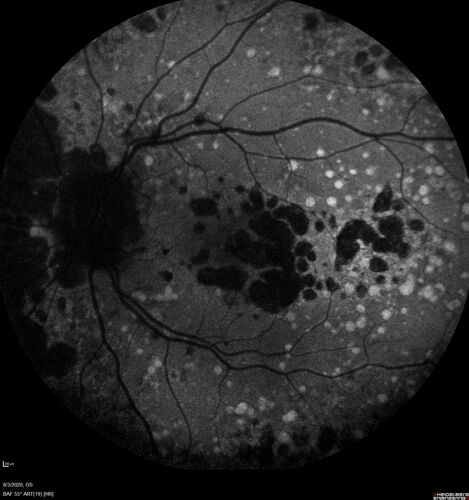

Dry AMD geographic atrophy and cystoid macular edema

79 year old vision is in for a checkup with no visual complaints in the left eye.  This is her better eye.  VA 20/200 OD, 20/50 OS.  3 years ago she had a CRVO in the left eye.  She is also diabetic for 20 years, has carotid insufficiency and anemia.  Left eye shows CME.  This was not treated and the vision improved to 20/40 over the next year although mild edema persisted.